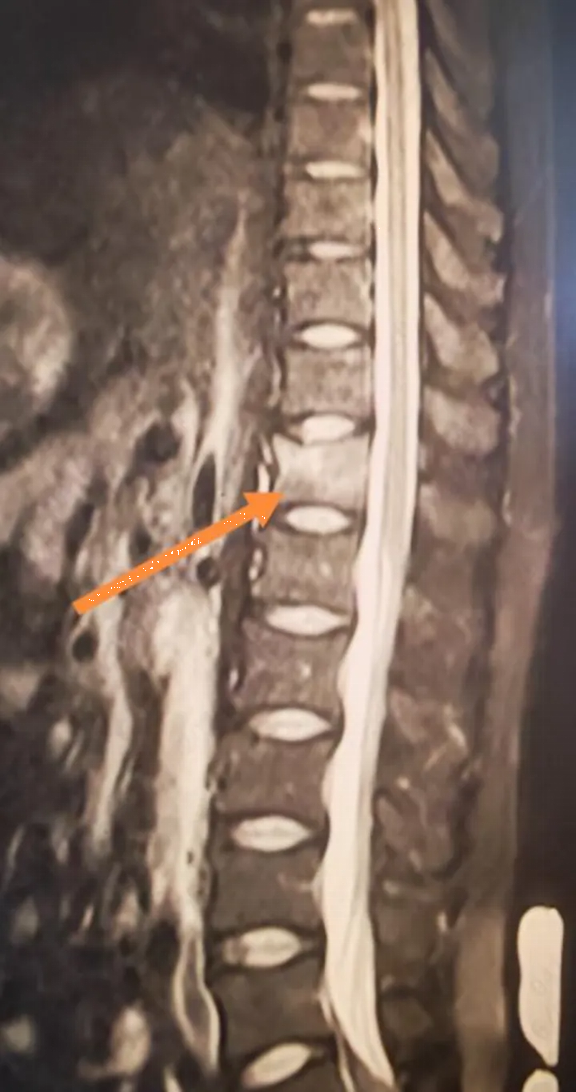

Sau khi khám kỹ, bác sĩ kết luận rằng anh Lý rất có thể bị gãy xẹp đốt sống. “Chắc chắn là có nhầm lẫn rồi! Tôi tập thể dục thường xuyên, xương khớp của tôi rất tốt, làm sao tôi có thể bị gãy xương chỉ vì nâng một quả tạ nhẹ chứ?”. Anh Lý cảm thấy chẩn đoán của bác sĩ có vẻ hơi phóng đại. Chỉ sau khi được bác sĩ thuyết phục kiên nhẫn, anh LÝ mới miễn cưỡng đi chụp MRI.

Kết quả chụp MRI khiến anh hoàn toàn sững sờ: gãy xẹp đốt sống T12.

Các xét nghiệm tiếp theo cho thấy kết quả còn gây sốc hơn chỉ số Z-score L1-L4 của anh Lý chỉ là -3,1, nghĩa là mật độ xương của anh thấp hơn so với hầu hết phụ nữ 60 tuổi. Một loạt các xét nghiệm đã loại trừ khả năng loãng xương thứ phát. Kết quả xét nghiệm cho thấy nồng độ vitamin D của anh Lý chỉ ở mức 10 ng/ml, thấp hơn nhiều so với tiêu chuẩn bình thường.